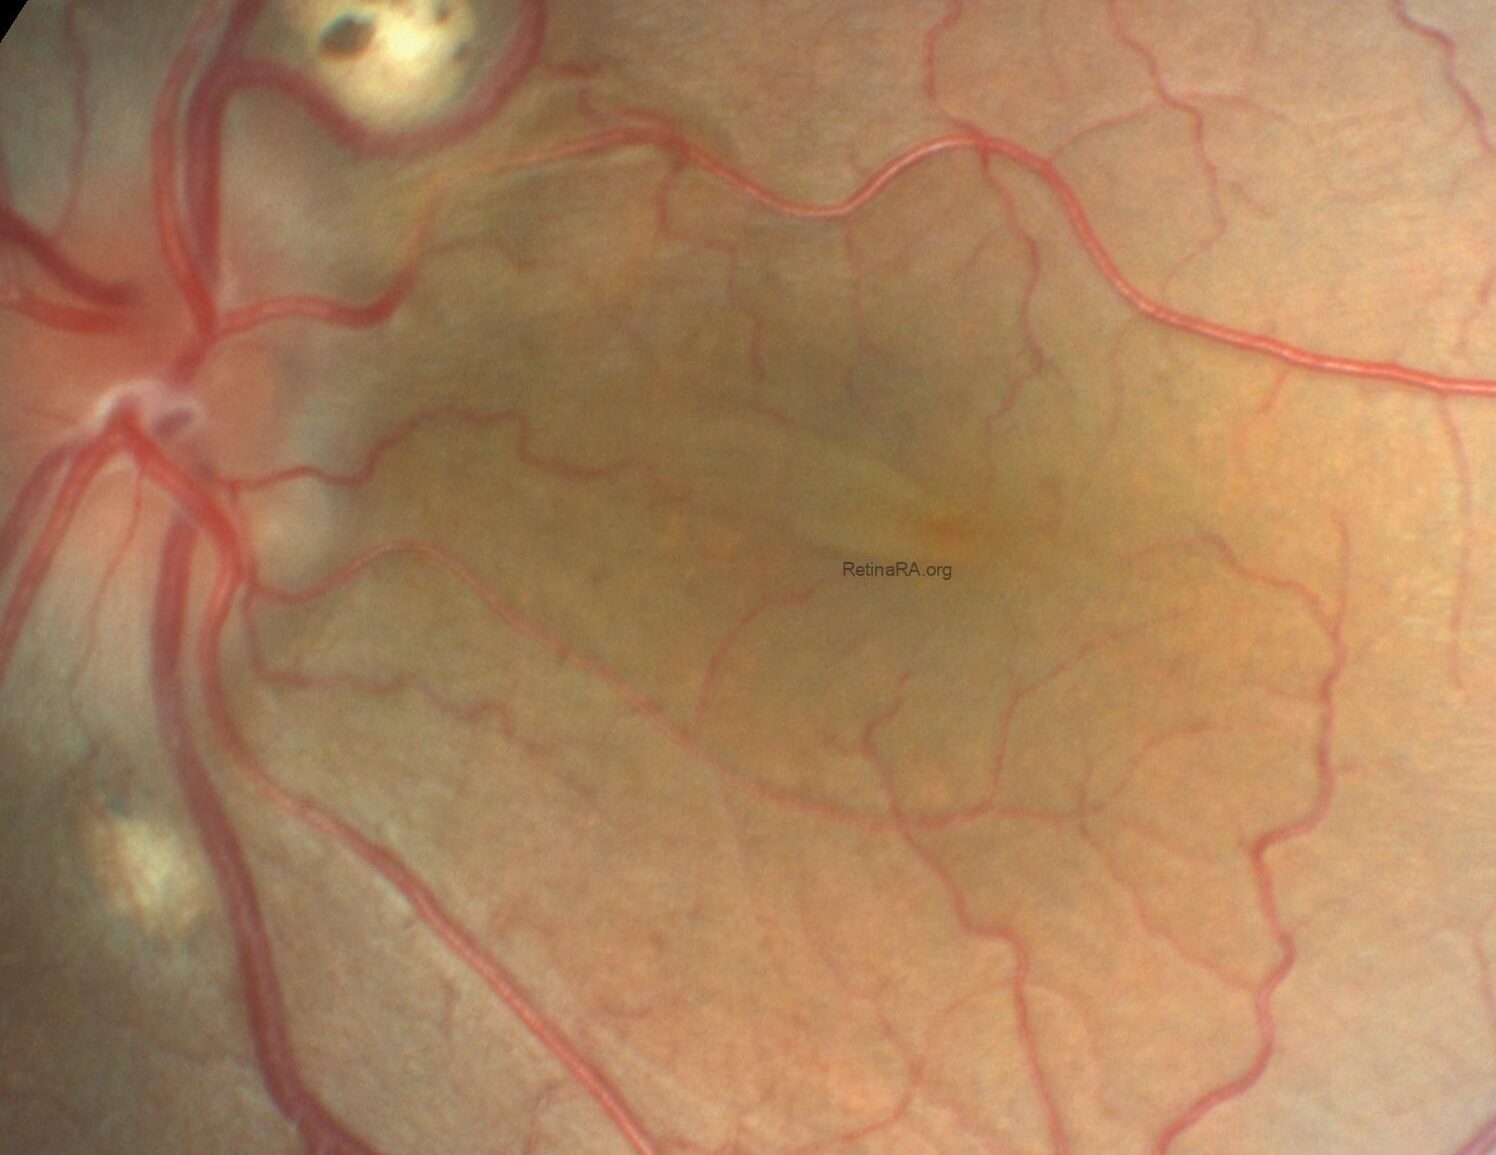

Gravitational tracks in chronic central serous chorioretinopathy: a multimodal imaging case

Patient history A 34-year-old male patient with a history of chronic central serous chorioretinopathy (CSC) [...]